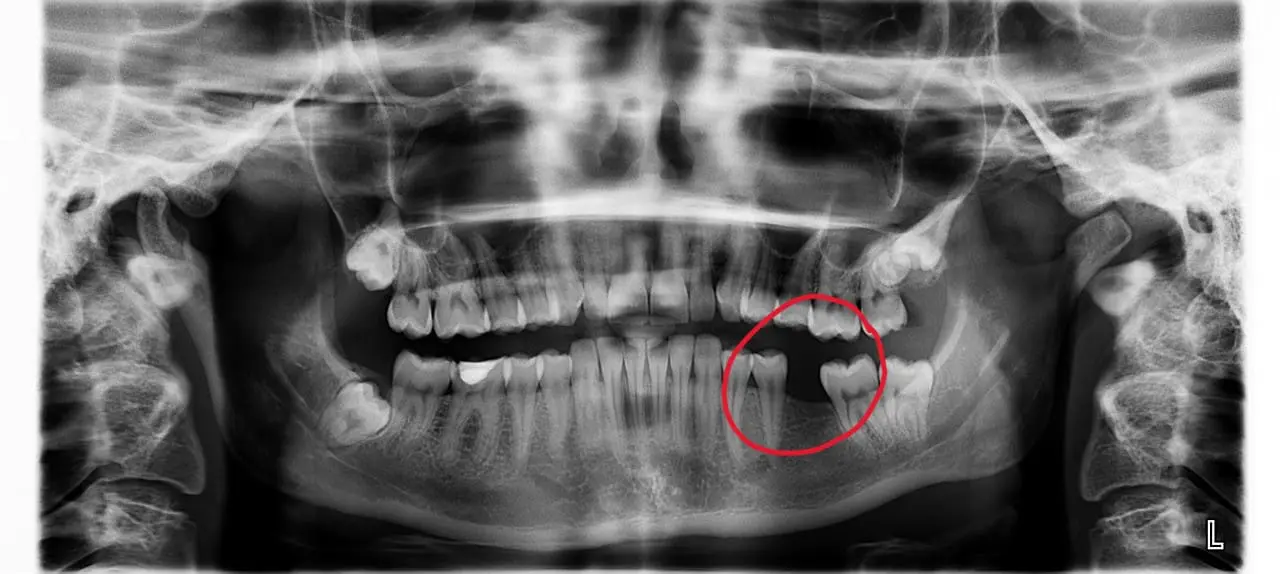

If it’s your first time, getting a dental crown can feel like a big step. It might seem a bit extreme compared to getting a filling, but sometimes it’s the only way to save a damaged tooth. Crowns are actually placed every day and are...